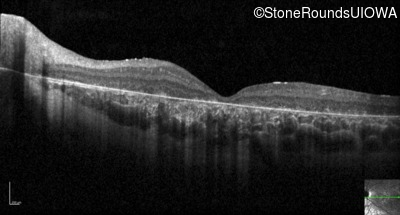

Optical Coherence Tomography - Right - 5/200 sc

Exemplar / OCT Stack